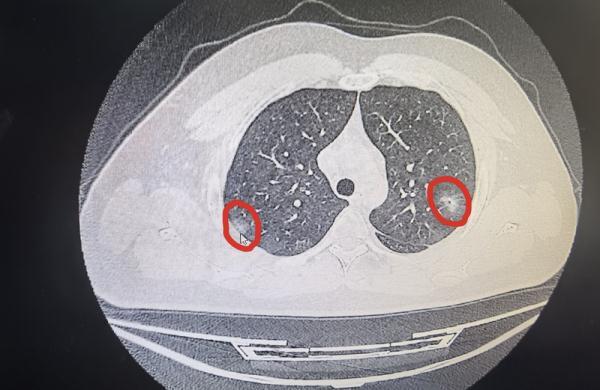

白肺病是指影像学表现,在拍片时肺呈现大片白色实变。一般来讲,肺部炎症比较重、渗出比较多,即白色影像区域面积达到70%到80%之时,在临床上被口语化称为“白肺”。正常的肺组织在影像学片上,表现为黑色。如果大片的甚至全部肺变成白色,称为白肺病。

轻微肺炎影像

“实际上我们在临床上看到的绝大部分的新冠感染者,还是以发热乏力、咽痛、鼻塞、流涕等上呼吸道症状为主,并没有涉及肺部的炎症,这部分人实际上是没有必要进行CT检查的。” 浙江大学医学院附属第一医院传染病科主任盛吉芳接受采访时表示。

“目前我们医院收治的患者基数不小,每天仅仅120急救车送过来的患者就有150个左右。确实有部分患者出现持续多日发烧不退,伴有呼吸困难、剧烈咳嗽等,我们认为肺部可能存在炎症时,会建议对其进行肺部CT检查,就在这部分患者当中,我们观察到肺部有渗出性病变(炎症)的患者比例也并不高,大约在10%至20%之间,虽然也有年轻人肺部受累,但主要还是合并有基础疾病、未接种疫苗的中老年人。”盛吉芳介绍。